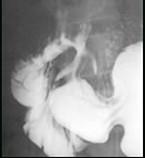

问题 男,32岁,中上腹空腹痛,进食后缓解,剑突下轻度压痛,钡餐检查如图,最可能的诊断是 ( )

选项 A.十二指肠癌 B.十二指肠憩室 C.十二指肠球部溃疡 D.十二指肠节段性肠炎 E.十二指肠结核

答案 C